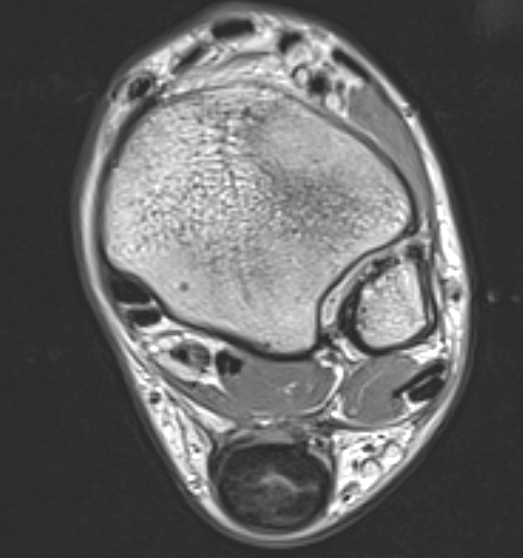

MRI

Tendon thickening

Thickening of the tendon with some intra-substance degeneration / partial tearing